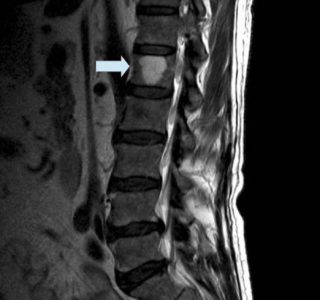

Εικόνα 2: Μαγνητική τομογραφία με αιμαγγείωμα του Ο1 σπονδύλου και η αντίστοιχη σχηματική απεικόνιση στην οποία φαίνεται ο τρόπος με τον οποίο ο αγγειακός αυτός καλοήθης όγκος αναπτύσσεται εντός του σπονδύλου

Τα αιμαγγειώματα της σπονδυλικής στήλης εμφανίζονται εντός των σπονδύλων, συνήθως στη θωρακική και οσφυϊκή μοίρα της σπονδυλικής στήλης και πολύ πιο σπάνια στην αυχενική μοίρα.

Η διάγνωση μπαίνει με τη μαγνητική και την αξονική τομογραφία. Η μαγνητική τομογραφία μετά τη χορήγηση σκιαγραφικού είναι η πιο ακριβής εξέταση.